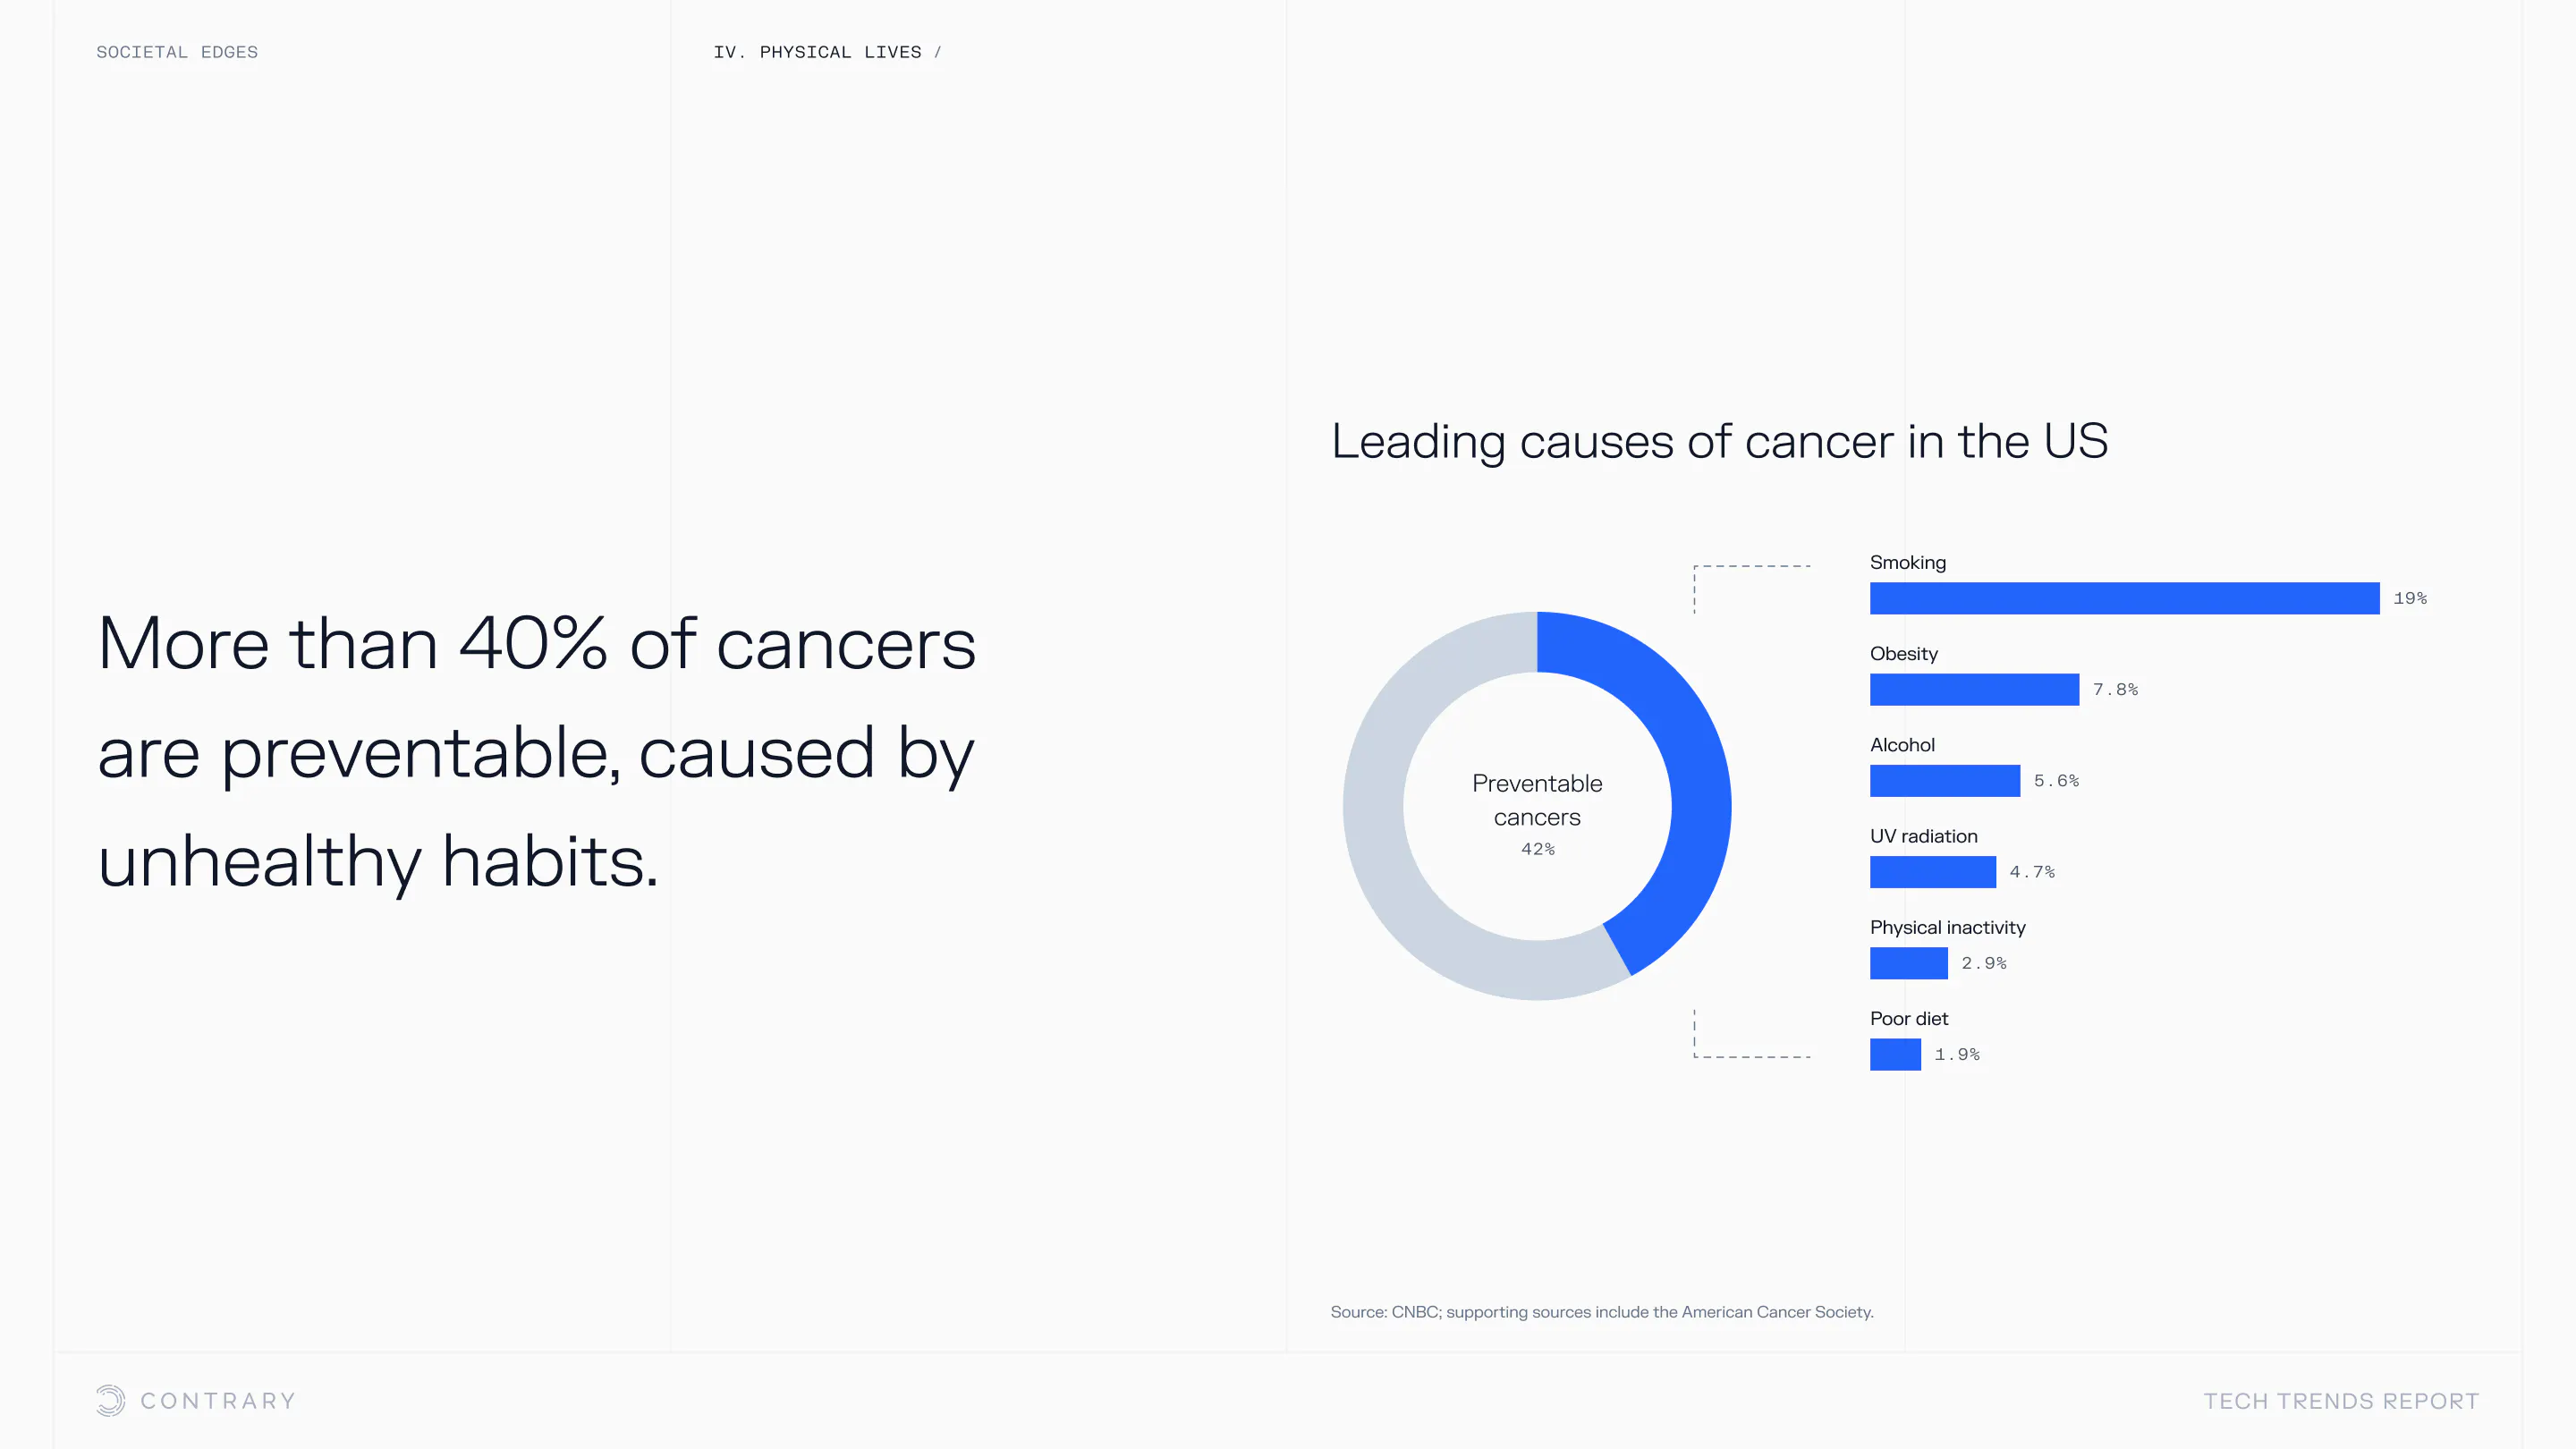

An aging population is bringing up a range of increased concerns, from mental health to disease control. Obesity and gastrointestinal cancers are plaguing younger generations. The cutting edge is tackling a system that has unhealthiness woven into it.